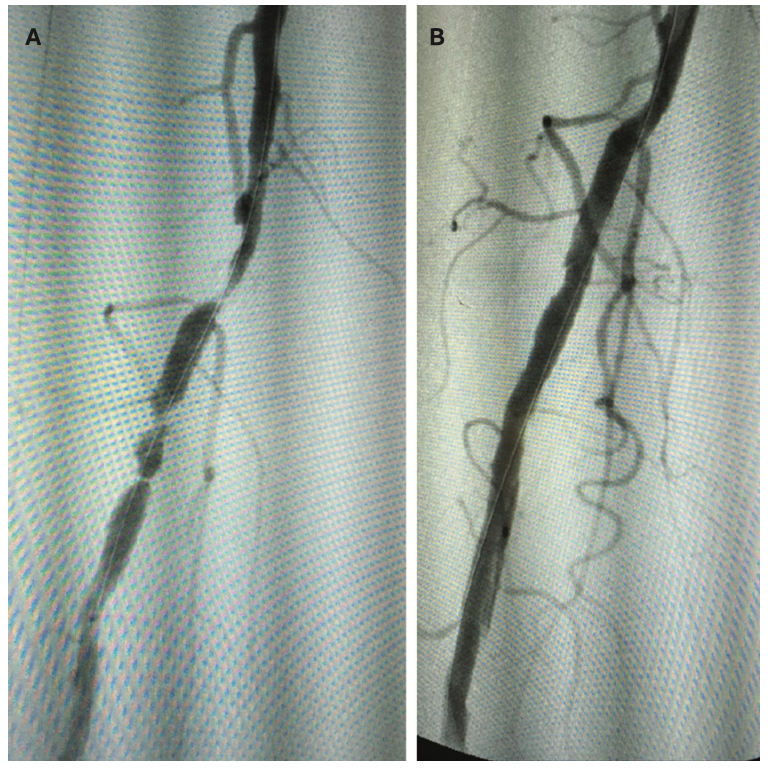

Once a patient presents with CLI, options of care are limited to amputation, peripheral vascular intervention (PVI), or a combination of both. Bypass may also be a consideration, dependent on the extent of blockage in the distal arteries, but often, once a patient presents with CLI, the disease state has progressed beyond the point of bypass being an option. Although there are risk factors with each treatment option, amputation carries a higher level of risk given the possibility of complications from an invasive surgical procedure, deep sedation, and the trauma of losing a limb. For below-the-knee amputations (BKA), a 2023 analysis by Beeson et al reported mortality rates of 4.18% at 30 days, 7.50% at 90 days, 10.88% at 1 year, and 16.67% at 5 years.3 Above-the-knee amputation (AKA) carries a higher risk of mortality, with rates at 9.27% at 30 days, 14.73% at 90 days, 19.40% at 1 year, and 24.49% at 5 years (Figure 1).3 Lower limb amputation has a significant impact on quality of life, as it not only affects the patient’s socioeconomic status and impairs mobility, but also has a systemic effect on the entire body. Patients can experience phantom limb pain, muscle contractures, fatigue, psychological issues with confidence and self-esteem, and have an increased fall risk due to changes in their center of gravity.

Shared decision-making should be foremost in the treatment plan, especially in the case of advanced disease and the existence of comorbidities. Palliative care is often a consideration when a patient has poor predicted outcomes for mortality and morbidity in early post-op stages. In these cases, combined peripheral vascular intervention and amputation are often considered to allow for limited revascularization through intervention allowing for amputation at a lower level; for example, amputation of the foot as opposed to a below-knee amputation. A team approach involving the patient and multidisciplinary providers is an absolute necessity, as treatment strategies involve cooperation across several specialties. Agreement on who is to provide the follow-up care should be incorporated into these decisions.